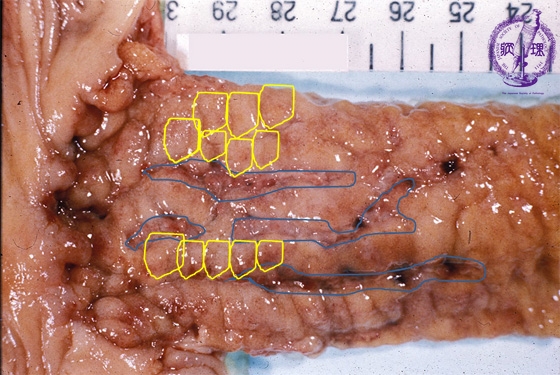

- ★(3)Crohn’s disease

Gross appearance: Linear ulcers (blue) and a cobblestone appearance (yellow) are distinctly seen.